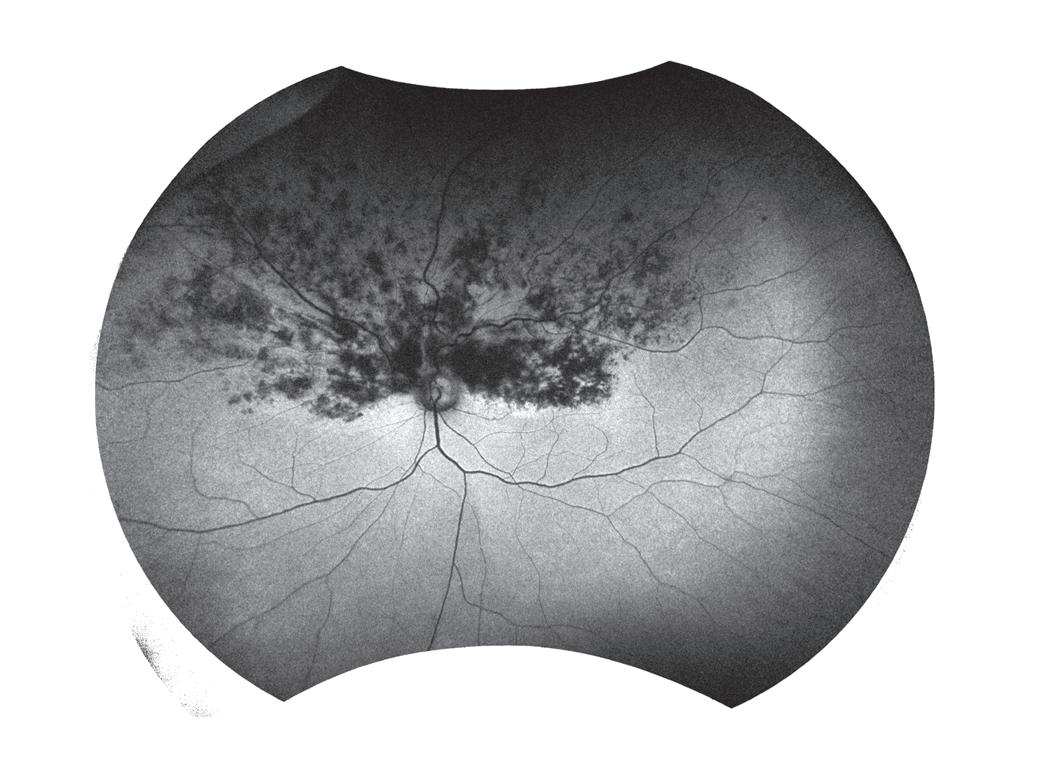

Women are significantly more likely than men to present with recurrent ocular toxoplasmosis, a study involving Flinders University has found.

Professor Justine Smith, from College of Medicine and Public Health at Flinders, was a joint senior author of ‘Impact of gender on clinical features and outcomes of ocular toxoplasmosis’ published in British Journal of Ophthalmology

The observational study involved 262 patients (139 women and 123 men) who presented to a tertiary referral uveitis service in Ribeirão Preto, Brazil, with serological and clinical evidence of ocular toxoplasmosis.

According to Smith and her fellow researchers, which also included Flinders University medical student Ms Matilda Lyons, approximately equal numbers of women and men had active versus inactive ocular toxoplasmosis.

In both women and men, most infections were remotely acquired.

Men were significantly more likely to present with primary active disease than women (24.4% versus 12.9%). Conversely, women were significantly

more likely to present with recurrent active disease than men (36.0% versus 28.5%).

According to the study’s results, one toxoplasmic retinal lesion was observed in more male eyes than female eyes (50.4% versus 35.3%), while women’s eyes were more likely to have multiple lesions than men’s eyes (54.7% versus 39.8%).

Lesions in women’s eyes were significantly more likely to occur at the posterior pole compared with those in men’s eyes (56.1% versus 39.8%). Measures of vision were similar for women and men.

“There were no significant differences in measures of visual acuity, ocular complications, and occurrence and timing of reactivations between the genders,” the authors noted.

They concluded that ocular toxoplasmosis has equivalent outcomes in women and men, with clinical differences in the form and type of disease, as well as characteristics of the retinal lesion.